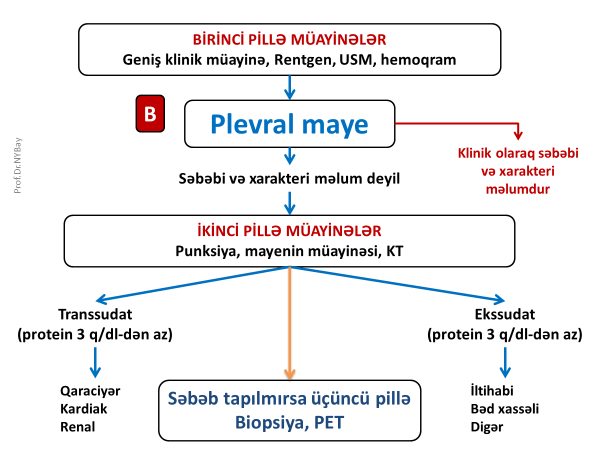

Plevral mayenin diaqnostikası

Plevrada mayeni rentgen göstərə bilər. Qabırğa-diafraqma cibinin düzləşməsi, plevrada homogen kölgəlik, Damuaze xətti mayenin rentgenoloji əlamətləridir. Qabırğa-diafraqma xəttinin düzləşməsi plevrada ən azı 250 ml mayenin olduğunu göstərir. Lakin, mayeni görmək üçün ən həssas müayinə USM-dir.

Plevral maye tapıldıqda ilk olaraq drenaj lazım olub-olmadığını həll etmək, sonra isə səbəbini axtarmaq lazmdır.

Massiv hidrotoraks (təngnəfəslik və hipoksemiya törədən maye) və irinli plevrit təcili drenaj tələb edir.

Plevral mayenin əksər hallarda klinik olaraq səbəbini təyin etmək mümkün olur. Səbəbi bəlli olmayan hallarda ikinici pillə müəyinələr aparmaq lazım gəlir ki, bunlara plevral mayenin analizi və KT aiddir.

Plevral mayenin biokimyəvi (protein, albumin, qlükoza, LDH, pH), mikrobioloji (qram boyama, kültür) və sitoloji müayinələri əksər hallarda mənşəyi və xarakteri barədə yetərli məlumat verə bilir. Klassik olaraq plevral maye transudat və eksudat olaraq iki yerə bölünür. Ürək, qaraciyər və böyrək yetməzliklərində adətən transudativ xarakterlı mayelər olur. Eksudativ maye isə adətən iltihabi və bədxassəli xəstəliklərdə daha çox rast gəlir. Bu xəstəliklərin müəyyənləşdirilməsində isə KT faydalıdır.

Eksudativ plevral mayelərdə önəmli məsələlərdən biri irinli iltihabın olub-olmamasıdır. Mayedə irintörədici mikrobların tapılması və ya pH-ın 7,2-dən aşağı olması irinli iltihaba xarakterikdir. Belə hallarda iltihabın əsas səbəbini də axtarmaq lazımdır. Aparılan ikinci pillə müayinələrə baxmayaraq səbəb tapılmırsa üçüncü pillə müayinələrinə üz tutmaq lazım gəlir (Şəkil 3).

Şəkil 3. Plevral mayedə diaqnostik yanaşma